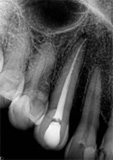

antes depois